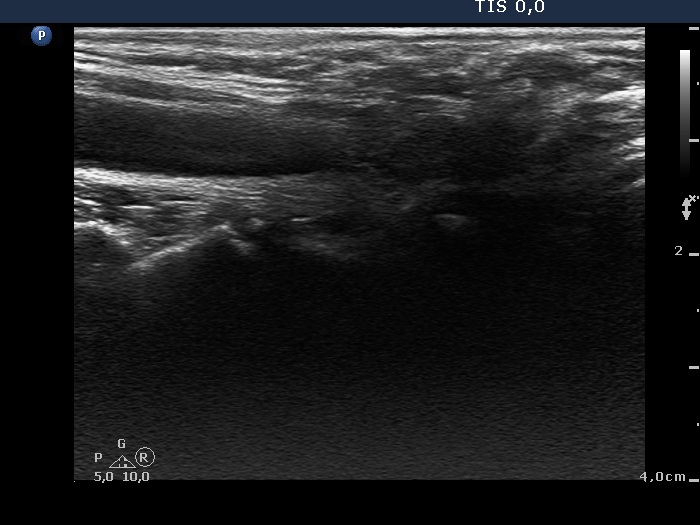

The operated thyroid - case 169 (ultrasonographic picture 2)

Right lobe, longitudinal view.